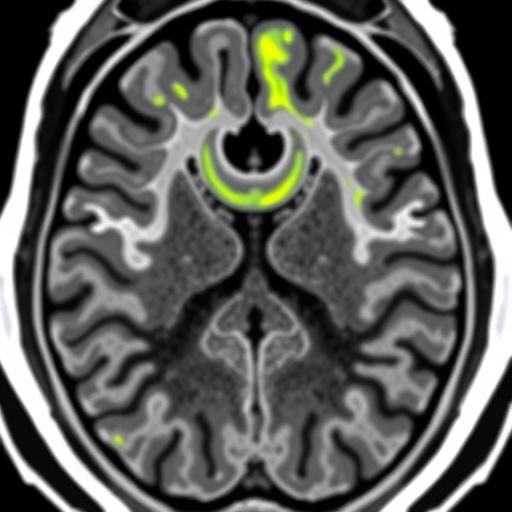

This multicenter, retrospective study compiled data from 206 HCC patients with pathologically confirmed diagnoses, sourced from three distinct hospitals, ensuring a diverse and robust dataset for model training and validation. The investigative team focused sharply on the hepatobiliary phase images (HBP) of gadoxetic acid-enhanced MRI, a specialized imaging sequence known for its superior liver lesion characterization. To harness the full potential of this imaging modality, three variations of deep learning architectures were meticulously developed and assessed: two-dimensional (2D), three-dimensional (3D), and a novel 2.5-dimensional (2.5D) deep multi-instance learning (MIL) model.

Among these approaches, the 2.5D MIL technique emerged as the most potent, ingeniously integrating information from all axial slices encompassing the tumor and surrounding peritumoral regions. This comprehensive slice selection allowed the model to capture both intratumoral heterogeneity and critical peritumoral microenvironmental features, which are hypothesized to play pivotal roles in MVI development. Remarkably, this approach outperformed conventional models with area under the curve (AUC) values reaching 0.802 in internal validation and 0.759 in the external test cohort, highlighting its strong generalizability across patient populations.

Building on these promising findings, the researchers extended their methodology by incorporating additional MRI sequences—T1-weighted fat-suppressed (T1WI-FS) and T2-weighted fat-suppressed (T2WI-FS) images—into a multimodal prediction framework. The synergistic use of these complementary sequences aimed to further refine the predictive algorithm by capturing distinct tissue contrasts and pathological signatures of MVI. This multimodal deep learning model demonstrated exceptional predictive capacity, with AUC values soaring as high as 0.954 in the training set, and sustaining robust performance metrics with AUCs of 0.857 and 0.788 in independent validation and test sets respectively.